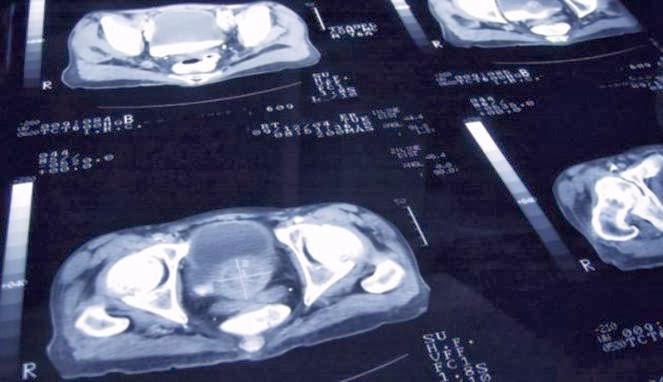

The verdict of prostate cancer for men is like doomsday. That means they have to undergo surgery or radiotherapy. The problem is, two ways out it is a gateway to a new affliction. Both are not without side effects. The most severe, can cause male infertility.

But now, researchers find ways to minimize medical treatment for patients with prostate cancer. The team was originally from England and America. Way they apply Prolaris named. Through a test, can be differentiated men with prostate cancer and is not dangerous.

The test works by analyzing the genetic alterations of the tumor. The patient is then given a score from -3 to +3. Who score higher, meaning that it has a more aggressive cancer cells. That's the priority for surgery or radiotherapy treatment.